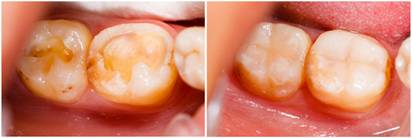

C1~C2のむし歯では、エナメル質に穴が開いたり、むし歯が象牙質の表層部に及んでいたりするので、 酸で侵された部分を削って修復材を詰めます。

最近では、エアタービン(歯を削る機械)でガリガリ削るのではなく、細かい金属の粉を吹きつけて削ったり、 薬でむし歯を軟らかくしてから、小さな器具で少しずつ掻き出すなど、削り過ぎないための工夫を施した治療も行われています。

詰め物として広く使われているのは、プラスチック樹脂のコンポジットレジンです。

パテのように軟らかいが、特殊な光を当てるとすぐ固まります。

色は数種類あるので、自分の歯に近い色を選ぶことができ、審美性(しんびせい)にも優れています。

このコンポジットレジンを、削った部分に直接詰めるのが「レジン修復」で、人目につく前歯や、 奥歯でも噛み合わせ部分だけ浅く削った場合などに用いられます。

型を取って詰め物をつくる必要がないので、通常、1回の治療で終了し、麻酔をする必要がない事が多いです。